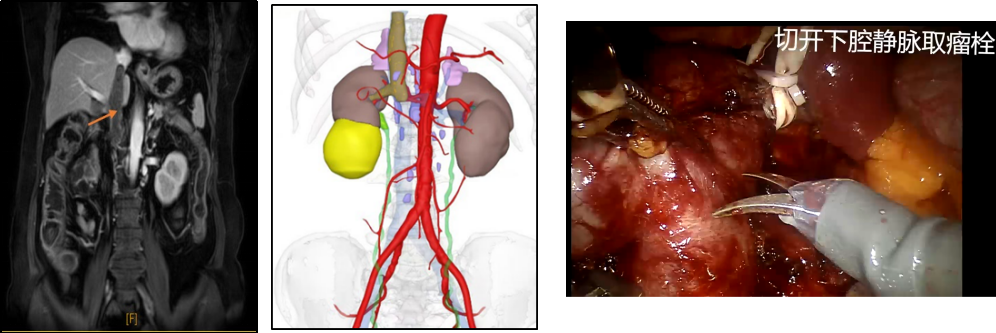

机器人辅助腹腔镜下肾癌根治术+Mayo II 级下腔静脉癌栓取出术

机器人辅助腹腔镜下肾癌根治术+Mayo II 级下腔静脉癌栓取出术肾癌合并下腔静脉癌栓手术被称为泌尿外科“皇冠上的明珠”,手术风险和难度极高,目前科室在开放肾癌根治+下腔静脉取栓手术的基础,常规实施“机器人辅助腹腔镜下肾癌根治术+Mayo II下腔静脉癌栓取出术”,近几年成功实施复杂的Ⅲ、Ⅳ级癌栓手术,荣获医院“技术创新一等奖”,成为区域复杂肾癌诊疗的典范。